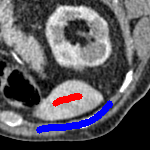

3 Alternative Selective Segmentation Models

We now introduce two recent methods that incorporate user input to perform selective segmentation. Each involves input in the form of foreground/background regions to indicate relevant structures of interest. An example of this can be seen in Fig. 18, where red regions indicate foreground and blue regions indicate background. We compare against the work of Nguyen et al. Nguyen:12 , which uses a similar convex relaxation framework to the proposed approach, and Dong et al. SRW , which uses a variation of the random walk approach. We summarise the essential aspects of each approach in the following.

In order to further establish the robustness of our method, we now introduce the results of testing our approach against competing interactive segmentation methods on a larger data set. The results are presented in Fig. 17, showing a boxplot of accuracy in terms of TC on a set of 30 CT images (excluding outliers). The target structure we consider is the spleen, as this consists of a relatively homogeneous foreground, appropriate for the approach considered. The data has been manually contoured providing ground truth data for the image set. We compare CAC Nguyen:12 and SRW SRW against our method with five variations of user input for each image. It is worth emphasising here that the input used in the tests is identical for each approach and was not refined in any way. It was designed to mimic what a user, unfamiliar with each approach, might select intuitively. A representative example for three images is shown in Fig. 18. This shows foreground (red) and background (blue) user input regions. For our method, we define the red region as as discussed in §1 and enforce hard constraints on the blue region. We refer to the results of the proposed approach using this input as Ours (i). We also include results of randomising the user input in an identical way to §7.3. For each image we generate 1000 simulated user input choices, which we present as Ours (ii). It is important to note that the difference between Ours (i) and (ii) is only the definition of . The method and parameters are fixed between each.